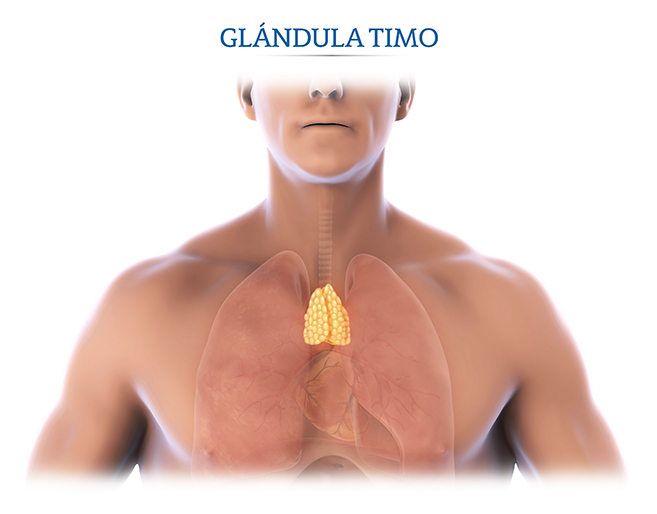

Фотографии вилочковой железы тимуса: структура и функции